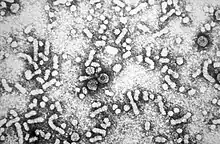

Viral infection

Viral infection with hepatitis C virus (HCV) or Hepatitis B virus (HBV) is the chief cause of liver cancer in the world today, accounting for 80% of HCC.[28][29][30] Men with chronic HCV or HBV are more likely to develop HCC than women with chronic HCV or HBV; however, the reasons for this gender difference is unknown. HBV infection is also linked to cholangiocarcinoma.[31] The role of viruses other than HCV or HBV in liver cancer is much less clear, even though there is some evidence that co-infection of HBV and hepatitis D virus may increase the risk for HCC.[32]

HBV and HCV can lead to HCC, because these viral infections cause massive inflammation, fibrosis, and eventual cirrhosis occurs within the liver.[33] In addition, many genetic and epigenetic changes are formed in liver cells during HCV and HBV infection, which is a major factor in the production of the liver tumors. The viruses induce malignant changes in cells by altering gene methylation, affecting gene expression, and promoting or repressing cellular signal transduction pathways. By doing this, the viruses can prevent cells from undergoing a programmed form of cell death (apoptosis) and promote viral replication and persistence.[28][34]

HBV and HCV also induce malignant changes by causing DNA damage and genomic instability. This involves the generation of reactive oxygen species, expression of proteins that interfere with DNA repair enzymes, and HCV induced activation of a mutator enzyme.[35][36]